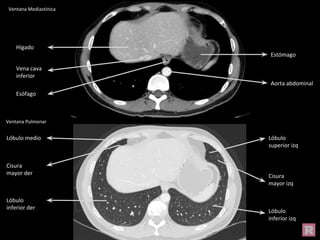

Ventana Pulmonar

Hígado

Estómago

Vena cava

inferior

Aorta abdominal

Esófago

Lóbulo medio

Cisura

mayor der

Lóbulo

inferior der

superior izq

mayor izq

inferior izq